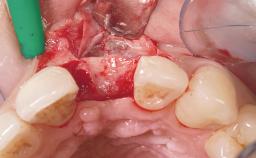

Immediate Placement of an Implant in a Maxillary Left Central Incisor Site

A 33-year-old female patient presented with an upper left central incisor that required extraction after a failed endodontic therapy. The tooth had been traumatized when the patient was a teenager and had undergone several endodontic treatments, including two apicectomy procedures. The patient was in good health and did not smoke. Clinical examination showed that the patient had a high lip line. In full smile, the gingival margins of the upper teeth were visible to the first molars. The gingival margins of central incisors 11 and 21 were only just showing. Examination of tooth 21 confirmed that the tooth was mobile and had hypererupted by 1 mm.

| Placement Protocol | Immediate implant placement |

| Tooth Site | Maxillary incisor or canine |

| Socket Integrity | Damage to one or more bone walls |

| Bone Volume | Damage to one or more socket walls |